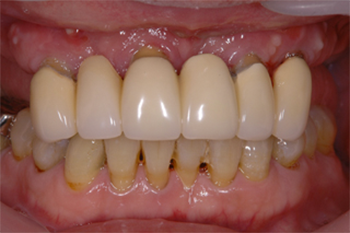

向かって右奥歯の根が露出してしまっています。

噛み合わせや不適切な治療や歯ブラシの仕方によって、歯周病が進行しきった状態です。

こうなってしまうと残念ながら救う手だてはありません。

前方の歯の詰め物、被せ物も決して精度高い治療とは言えません。歯周病は早期発見・早期治療が大切なのです。